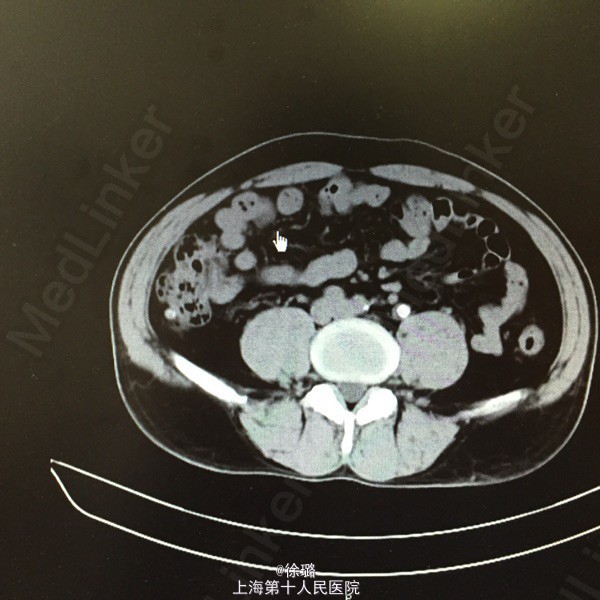

患者XXX,男,52岁。 主述:腰部酸胀不适半年余。 病史:患者半年前始无明显诱因出现腰部酸胀不适,左侧腰部酸胀稍明显,无恶心呕吐,不伴发热、黄疸、腹泻、黑便及肉眼血尿,症状轻,未诊治,今患者至当地医院查体,查B超示:双侧输尿管扩张伴肾积水,双侧输尿管上段结石。患者为进一步治疗,来我院就诊,拟“双侧输尿管上段结石”收住入院。

查体:双肾区无明显膨隆,左肾区无明显压痛,叩击痛可疑阳性,右肾区无明显压痛,叩击痛阴性,左侧输尿管走行区下段叩击痛阳性,右侧输尿管走行区下段叩击痛阴性,膀胱区无充盈,无压痛,尿道口无红肿。前列腺指检:前列腺未及增大,质韧,无明显结节,压痛阴性,指套无血染。 辅检:B超示:双侧输尿管扩张伴肾积水,双侧输尿管上段结石。尿路平片:1.双侧输尿管上段走行区致密影,考虑输尿管结石可能。2:盆腔耻骨联合上方投影区钙化影,前列腺钙化?请结合其他检查。3.CT:两侧输尿管上段结石,致其上输尿管及肾盂肾盏明显扩张积液。

诊断:双侧上段输尿管结石 治疗:1.完善各项术前检查。2.择期行输尿管镜激光碎石术。